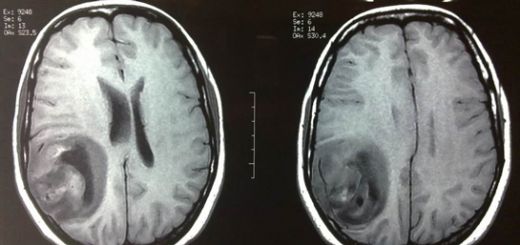

Kötü Huylu Beyin Tümörü Belirtileri ve Tedavisi Beyin tümörleri, beyin hücrelerinin anormal şekilde büyümesiyle oluşan kütlelerdir. Kötü huylu beyin tümörleri, malign (kötü huylu) özellikler gösterir ve genellikle hızlı bir şekilde büyüyerek çevre dokulara zarar verebilir. Bu makalede, kötü huylu beyin tümörlerinin belirtileri, tanısı, tedavi yöntemleri ve hastaların yaşam kalitesi üzerindeki etkileri ele alınacaktır. Kötü Huylu Beyin Tümörlerinin Belirtileri Kötü huylu beyin tümörlerinin belirtileri, tümörün türüne, boyutuna ve konumuna bağlı olarak değişiklik gösterebilir. Genel olarak aşağıdaki belirtiler gözlemlenebilir:

Bu belirtiler, kötü huylu beyin tümörü olan hastalarda sıklıkla görülse de, başka sağlık sorunlarıyla da ilişkili olabilir. Bu nedenle, bu belirtiler gözlemlendiğinde bir sağlık uzmanına başvurmak önemlidir. Tanı ve Tanı Yöntemleri Kötü huylu beyin tümörlerinin tanısı, genellikle aşağıdaki yöntemlerle konur:

Bu yöntemler, hastalığın kesin tanısını koymak için hayati öneme sahiptir. Tedavi Yöntemleri Kötü huylu beyin tümörlerinin tedavisi, tümörün türüne, evresine ve hastanın genel sağlık durumuna bağlı olarak değişiklik gösterebilir. Genel tedavi yöntemleri şunlardır: